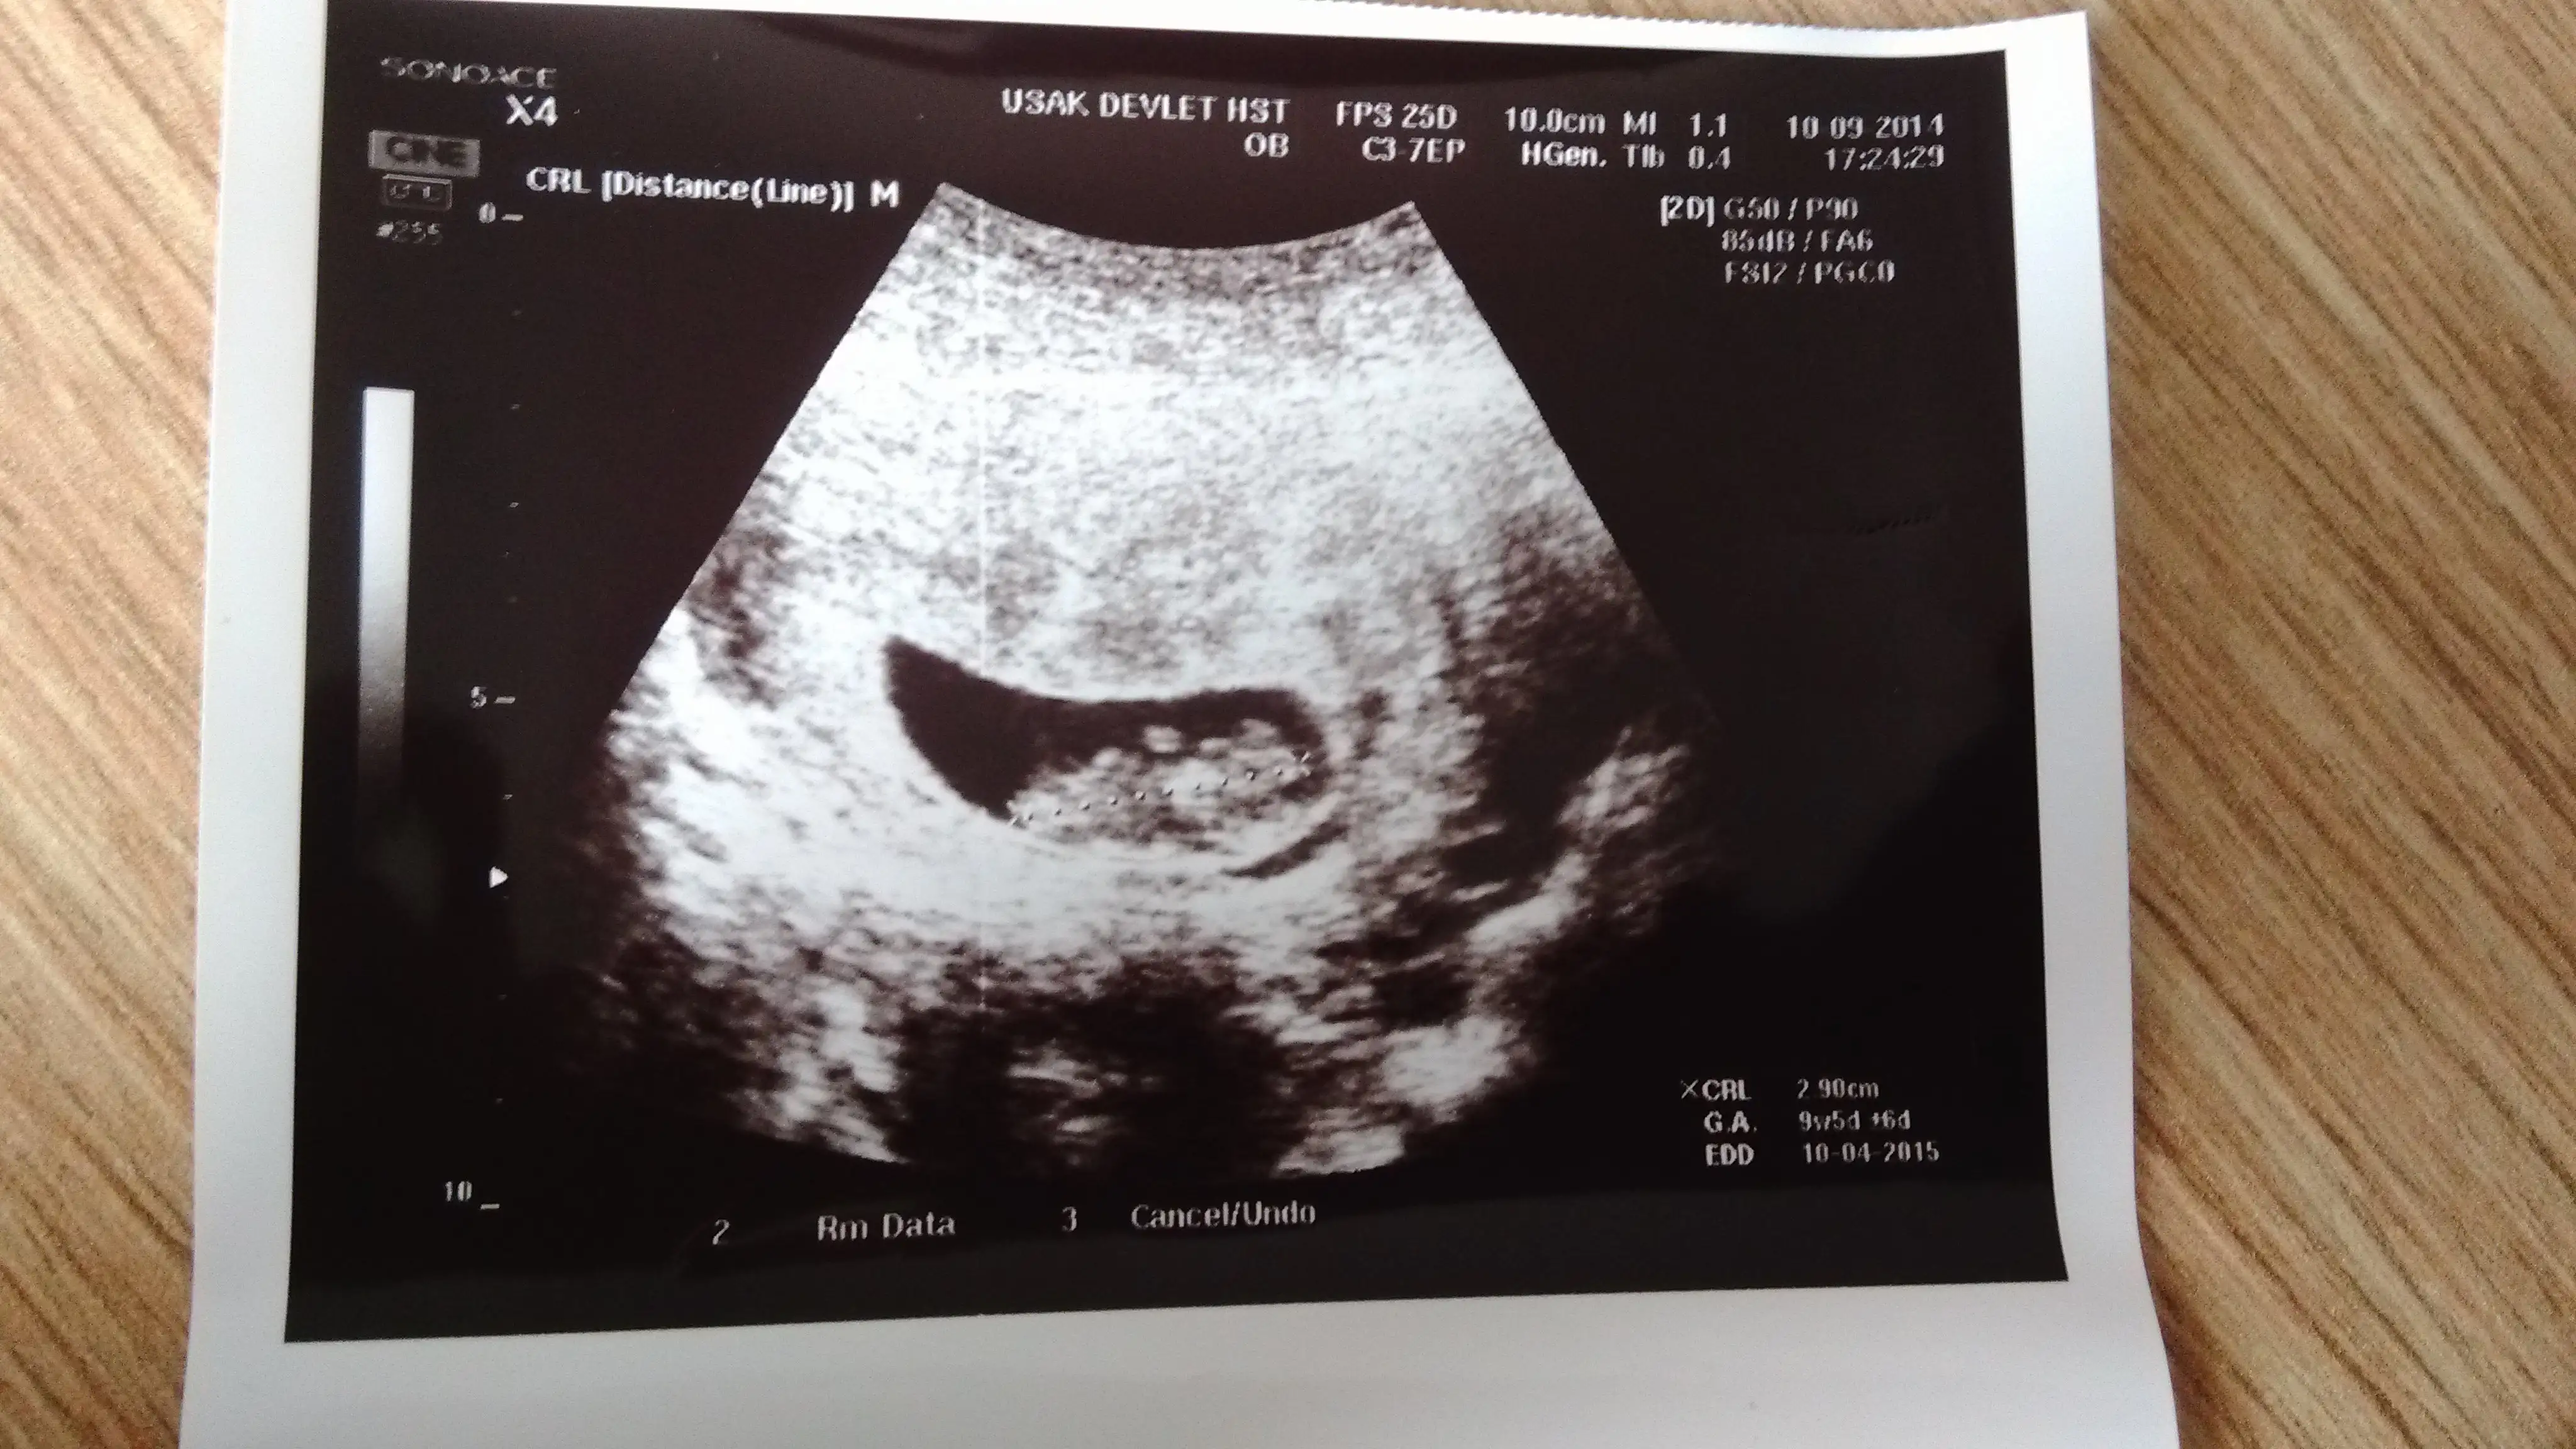

benimkine de bakar mısınız doktor erkek dedi ama daha 12+3 haftalık o yüzden tam kendimi kaptırmak istemiyorum

Eklentiler

• image.webp

34,8 KB · Görüntüleme: 231

42,5 KB · Görüntüleme: 231

63,4 KB · Görüntüleme: 229